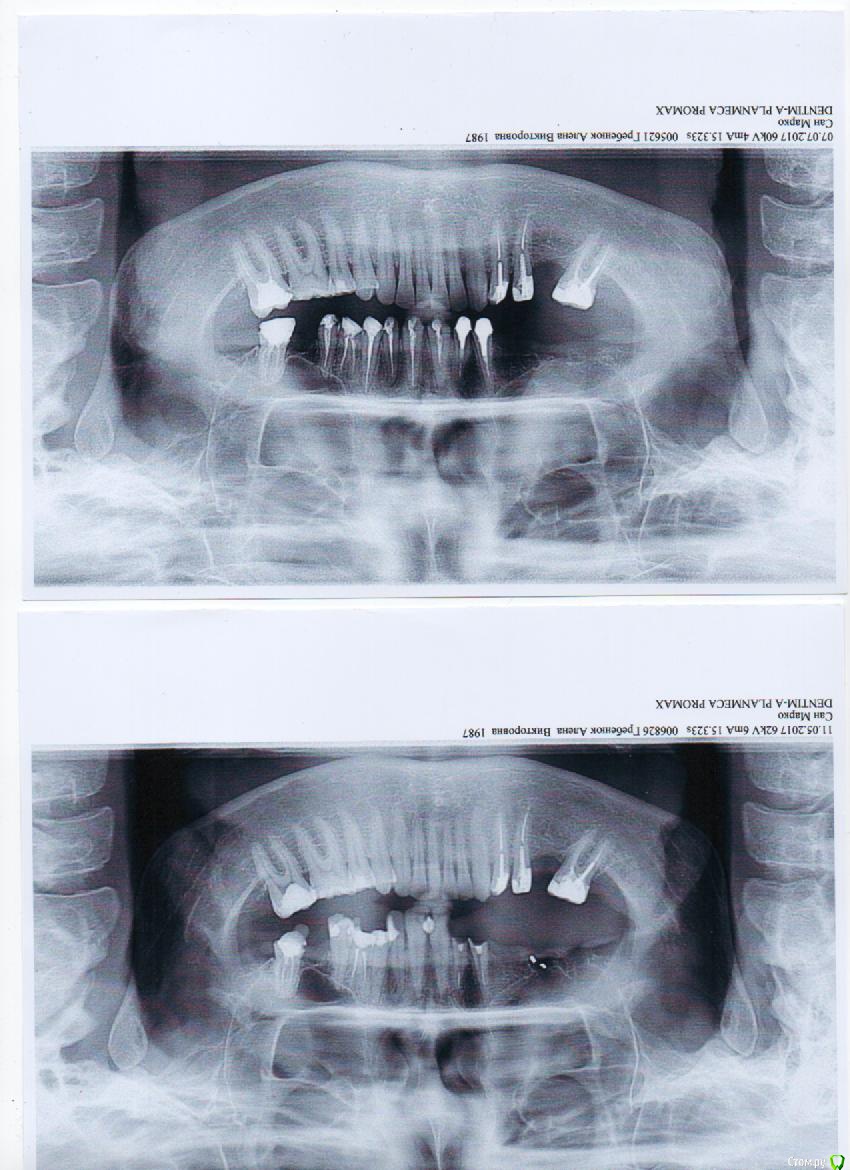

Аленчик Опубликовано 11 июля, 2017 Поделиться Опубликовано 11 июля, 2017 (изменено) Помогите пожалуйста советом и рекомендациями в лечении. Очень нужна помощь, как можно большего количества специалистов. Очень сильно намучилась уже со своими зубами.Ситуация моя в следующем. Сейчас приготовили верхнюю челюсть под протезирование, мост на 12 шт (2 сбоку буду навесные).На примерке (позавчера) метал. каркаса при надевании очень сильно болел 13 зуб. Врач вчера и позавчера уколы над зубом, сказал, что канал леченный, на всякий случай, что бы не было воспаления, что колол не спрашивала. Сейчас еще несколько зубов разболелось: 12,13, 21,22,23. В основном при накусывании. Сегодня 21 при откусывании пищи странно вообще отреагировал. Как будтто зуб чем то пропилили. Делала снимок ,а на рентгене сказали, что не все каналы пройдены. На снимке видно пространство в канале после вкладки.Лечащий врач сказал, что все каналы хорошо закрыты, а под вкладкой цемент, который на снимке не видно. Отправляю снимки до и после лечения, подписаны по датам. Уже скоро будут мост на временный цемент. Врач сказал, что пожожу, привыкну, все перестанет болеть, потом на постоянный поставит. Я очень переживаю, что если каналы не закрыты, то могут быть со временем ( и через пол года, и 2 г.) проблемы с корнями. Начиталась, и боюсь потом этих осложнений. Посмотрите пожалуйста снимки. Скажите, все ли каналы хорошо запломбированы, может ли под вкладкой быть такое пространство.Если что-то не так, скажите на каких зубах и корнях.На снимке между 12 и 13 каналами, и возле 22 было темное, похожее на воспаление. Делала на них прицельные (к сожалению у врача остались снимки, не могу отправить) , на них вроде этого темного нет. Изменено 11 июля, 2017 пользователем Аленчик 1 Ссылка на комментарий

dok1 Опубликовано 15 июля, 2017 Поделиться Опубликовано 15 июля, 2017 Почти все каналы запломбированы неудовлетворительно. Боли могут быть из-за этого. Без временных коронок протезирование невозможно по современным стандартам. Металлопластмассовая конструкция - путь вникуда. Чревато быстрой потерей опорных зубов. Меняйте либо тактику протезирования, либо врача. Ссылка на комментарий